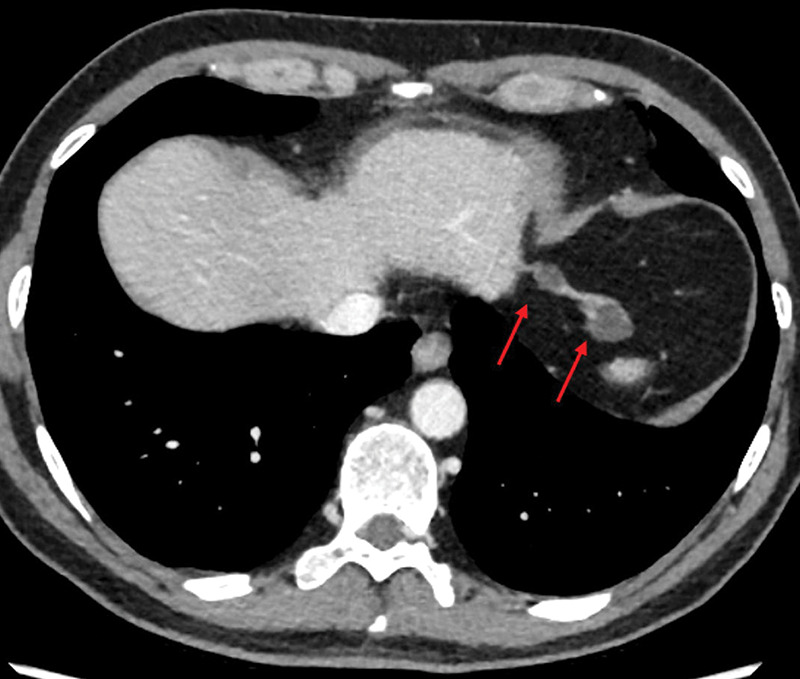

Hepatic Cysts in the Left Triangular Ligament: A Rare Finding with Potential Diagnostic Challenges.

肝囊肿在左三角韧带:一个罕见的发现与潜在的诊断挑战。